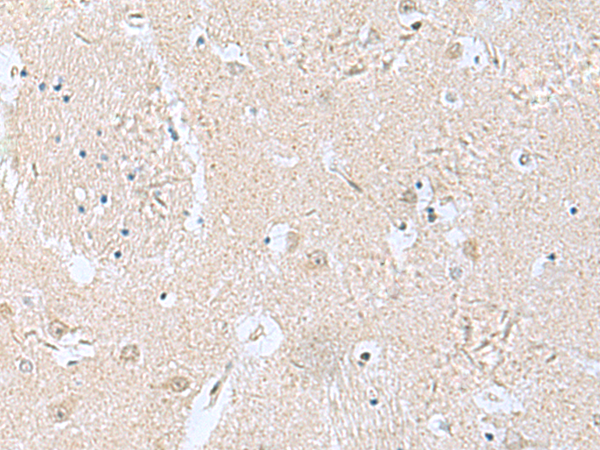

分类: 科研抗体货号: P10235别名: PHP; PHP14; CGI-202; HSPC141; HEL-S-132P应用: WB,IHC反应种属: Human, Mouse